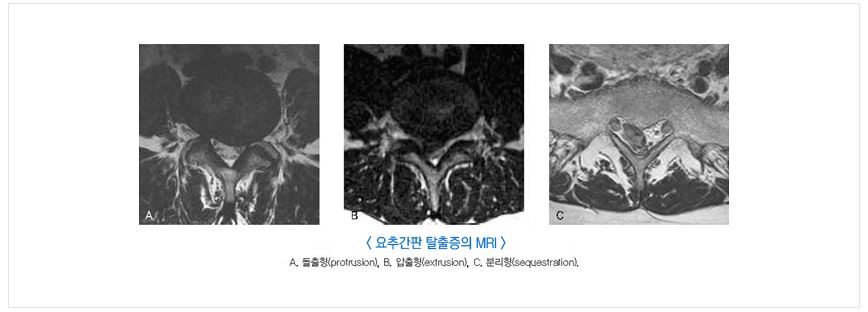

2.3. 허리디스크의 진단

허리 디스크의 정확한 진단을 위해서는 병력 청취, 신체검사, 영상 진단 등이 필요합니다. MRI나 CT 스캔을 통해 디스크의 상태를 확인할 수 있으며, 필요한 경우 신경 전도 검사를 통해 신경 손상 여부를 평가합니다.

자기 공명촬영

디스크의 구조와 신경을 누르는 정도를 알 수 있습니다.